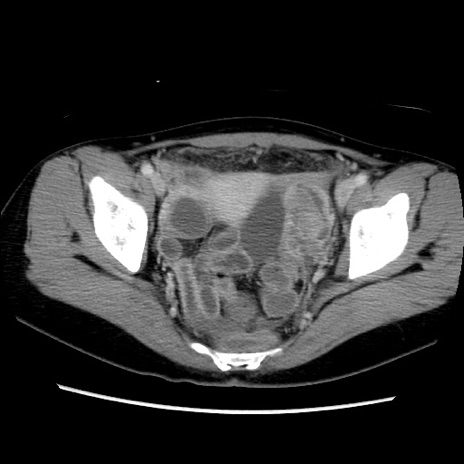

症例39(横断像)

【症例】40歳代女性

【主訴】上下腹部痛

【現病歴】2日目から下腹部痛あり。夜間は痛みで眠れなかった。昨日より上腹部痛と下痢が出現。臥位で痛みは軽快したため、休んでいた。本日になって臥位でも立位でも痛みが強くなってきたため救急要請。

【既往歴】子宮内膜症

【身体所見】部:平坦・軟、左上下腹部に圧痛あり、反跳痛あり。

【データ】WBC 21800、CRP 26.78